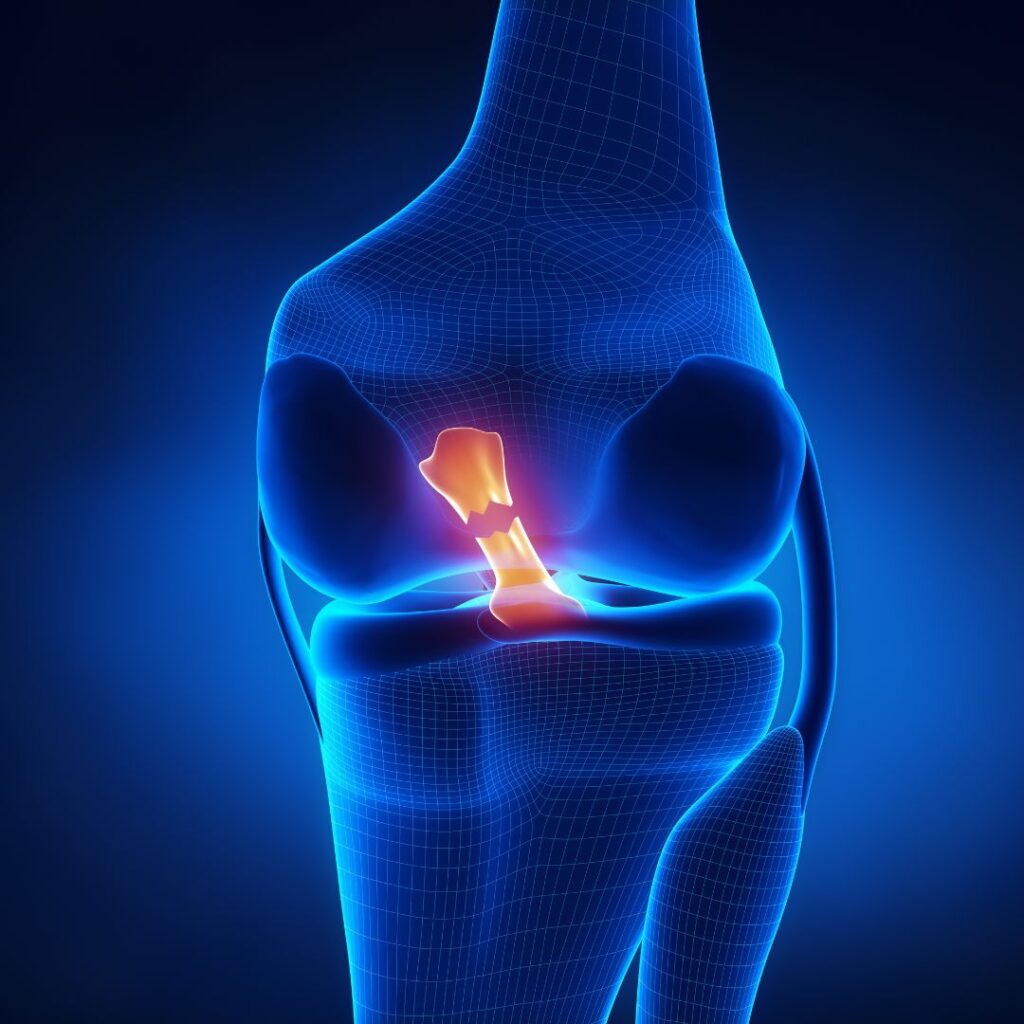

ACL Repair (Keyhole Surgery)

Anterior Cruciate Ligament (ACL) injuries are common in athletes and active individuals, often causing pain, instability, and limited mobility. ACL Repair (Keyhole Surgery) is a minimally invasive procedure performed by Dr. Lokesh Dabral to reconstruct the torn ligament and restore knee stability. Using advanced arthroscopic techniques, the surgery ensures precise repair, minimal tissue damage, faster recovery, and long-term joint function. Post-operative rehabilitation focuses on regaining strength, flexibility, and confidence, helping patients return to sports and daily activities safely